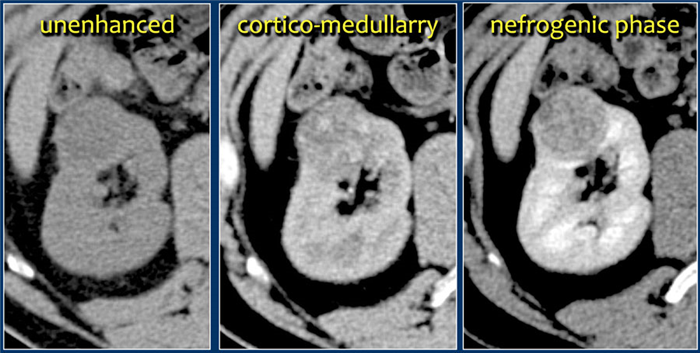

Светло-клеточная карцинома.

Светло-клеточная карцинома почек составляет 70% случаев рака почек.

Данная опухоль чаще больших размеров и прорастает из почечной коры. Светло-клеточная карцинома является гиперваскулярным образованием с неоднородным содержимым, как следствие некроза, кровоизлияний, кальцинирования или образование внутри кист. В редких случаях почечно-клеточная карцинома содержит внеклеточный жир, соответственно, образование с включением жира и кальцинатов следует рассматривать, как почечно-клеточную карциному.

Характерной особенностью светлоклеточной карциномы явлечётся значительное усиление в кортикомедуллярную фазу.

Хотя трудности бывают, когда образование небольших размеров и локализуется в почечной коре, которая также хорошо контрастируется.

Поэтому нефрографическая фаза при образованиях такой локализации и размеров является для оценки наиболее важной так, как паренхима контрастируется гомогеннее и сильнее, чем опухоль, что хорошо заметно на ниже приведённых изображениях.